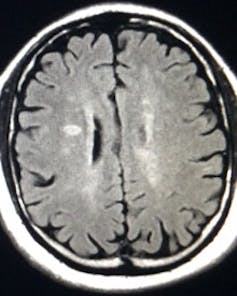

Multiple sclerosis causes damage to the myelin sheath that protects nerves in the brain and spinal cord. (By Stephanie021299 - Own work), CC BY-SA